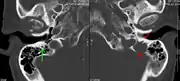

The diagnostic examination of a person with suspected multiple myeloma typically includes a skeletal survey. This is a series of X-rays of the skull, axial skeleton, and proximal long bones. Myeloma activity sometimes appears as "lytic lesions" (with local disappearance of normal bone due to resorption). And on the skull X-ray as "punched-out lesions" (raindrop skull). Lesions may also be sclerotic, which is seen as radiodense.[59] Overall, the radiodensity of myeloma is between −30 and 120 Hounsfield units (HU).[60] Magnetic resonance imaging is more sensitive than simple X-rays in the detection of lytic lesions, and may supersede a skeletal survey, especially when vertebral disease is suspected. Occasionally, a CT scan is performed to measure the size of soft-tissue plasmacytomas. Bone scans are typically not of any additional value in the workup of people with myeloma (no new bone formation; lytic lesions not well visualized on bone scan).

A CT of the brain revealed a lytic lesion in the left temporal bone (right side of image), and petrous temporal bones involving the mastoid segment of the facial nerve canal. Red arrows: lesion; green arrow: normal contralateral facial nerve canal. The lesions are consistent with a myeloma deposit.